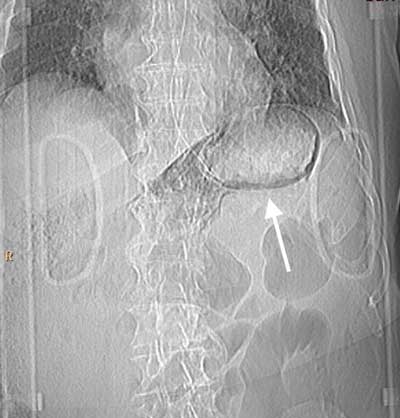

Figure 1

Topogram preliminary to the CT scan. Linear gas shadows in the upper left abdominal region (arrow), apparently round the stomach.